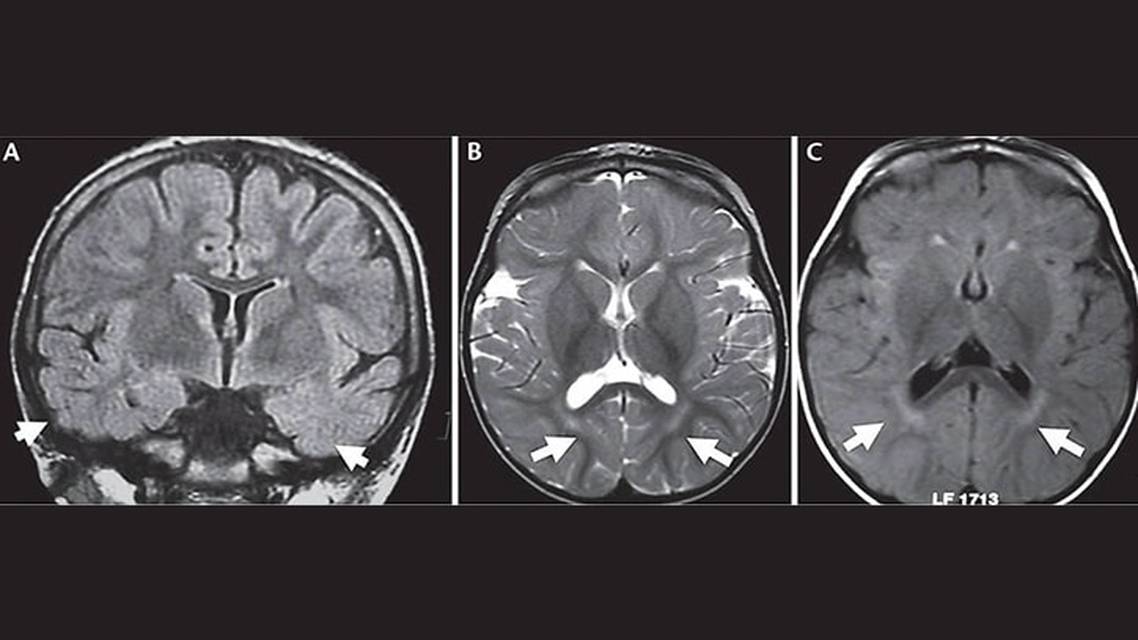

Many people with CDD present with early-onset, drug-resistant epilepsy, and severe global neurodevelopmental delays.7,9,11 Epileptic encephalopathy ranges from mild to severe forms, with severe forms being most common. The seizures associated with CDD are epileptic spasms in either the presence or absence of hypsarrhythmia, as well as tonic, myoclonic, generalized, or focal to bilateral tonic-clonic seizures. Generalized hypotonia, visual cortical blindness, and associated comorbidities have also been reported. Sleep disturbances, recurrent infections (respiratory and gastrointestinal), and severely impaired speech and gross motor function can occur.7,8 Notably, similar to typical Rett syndrome, most girls and women with CDKL5 variants have been observed to have hand stereotypies, as seen in Ms K.12 Also as in Ms K, brain MRI is typically abnormal, with cerebral atrophy and posterior white matter abnormalities reported in the majority (Figure).12